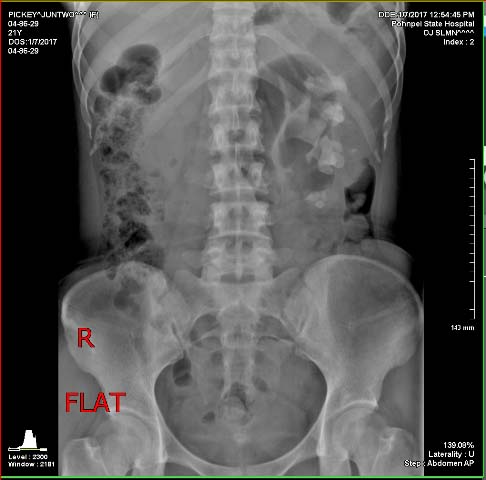

2016-133